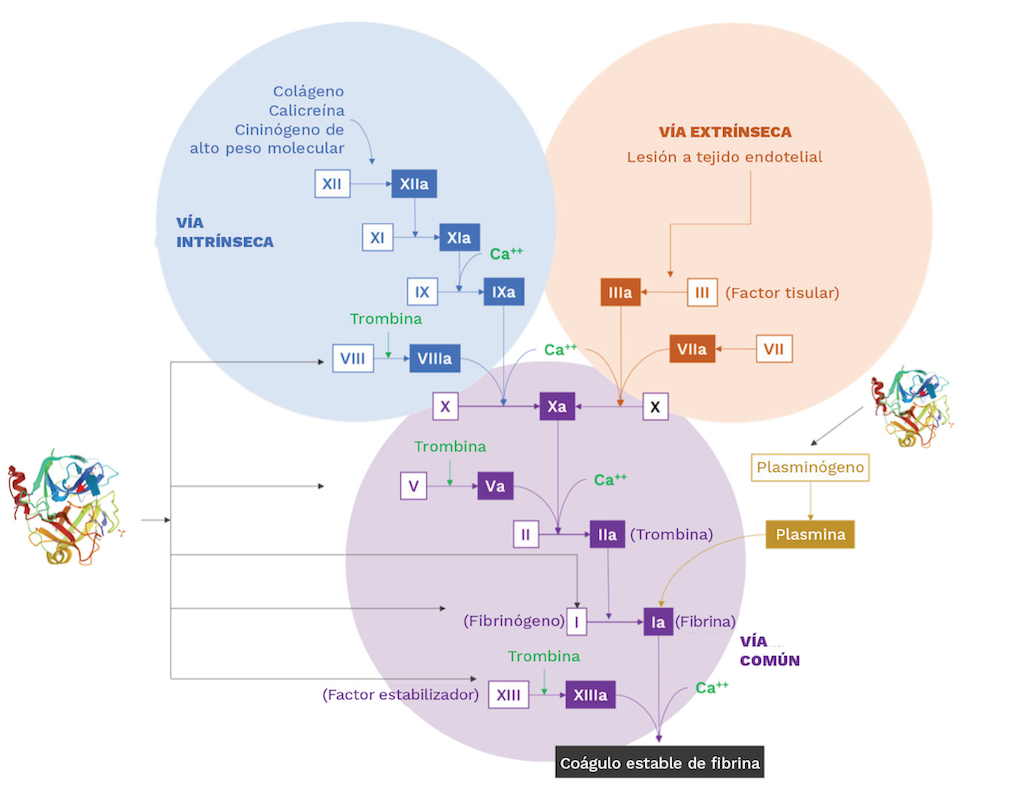

Actividad anticoagulante

Las enzimas PLA2, según su potencia anticoagulante, se clasifican en enzimas fuertes, débiles y no anticoagulantes. Las PLA2 fuertemente anticoagulantes inhiben la coagulación sanguínea a concentraciones bajas (<2 µg/mL), mientras que las PLA2 débilmente anticoagulantes muestran efectos entre 3 y 10 µg/mL. Algunas PLA2 del veneno no prolongan significativamente los tiempos de coagulación, incluso a 15 µg/mL; y, por lo tanto, se clasifican como enzimas no anticoagulantes [138].

Los primeros estudios sobre PLA2 sugieren que la actividad catalítica es necesaria para sus efectos anticoagulantes [137]. Sin embargo, estudios recientes proponen que las PLA2 fuertemente anticoagulantes actúan a través de mecanismos tanto enzimáticos como no enzimáticos, siendo estos últimos mediados por un «sitio anticoagulante». Kini et al. [138] propusieron la posición de este sitio en la estructura tridimensional de las PLA2, que se encuentra entre los residuos 53 y 76, y está cargada positivamente, mientras que las PLA2 con actividad débil o no anticoagulante tienen un predominio de cargas negativas o neutras en esta región [136,138].

Sin embargo, Stefansson et al. [139] propusieron un mecanismo no enzimático para las PLA2 anticoagulantes [139]. El estudio demuestra que una PLA2 del veneno de la cobra escupidora de cuello negro (Naja nigricollis) que tiene fuertes propiedades anticoagulantes, se une al factor de coagulación Xa, bloqueando la activación adicional de la protrombina. Faure et al. [149] propusieron un modelo estructural para la interacción entre las PLA2 y el factor de coagulación Xa. Varios enfoques bioinformáticos proponen que los residuos específicos 2, 3 y 7 de la hélice 1; 16, 18, 19, 23, 24, 31–34 del bucle de unión a Ca2+; 53, 59, 60, 69, 70 de la hélice 3; y 118, 119, 121–124, 129–131 y 133 de las láminas β, se unen entre sí. El conocimiento aceptado actualmente propone que las PLA2 del veneno de serpiente pueden provocar su actividad anticoagulante a través de mecanismos tanto enzimáticos como no enzimáticos [141,142].